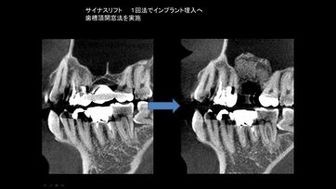

ソケットリフトにより骨造成を行った症例

サイナスリフトにより上顎洞の横から

骨に穴を開け骨造成を行った症例